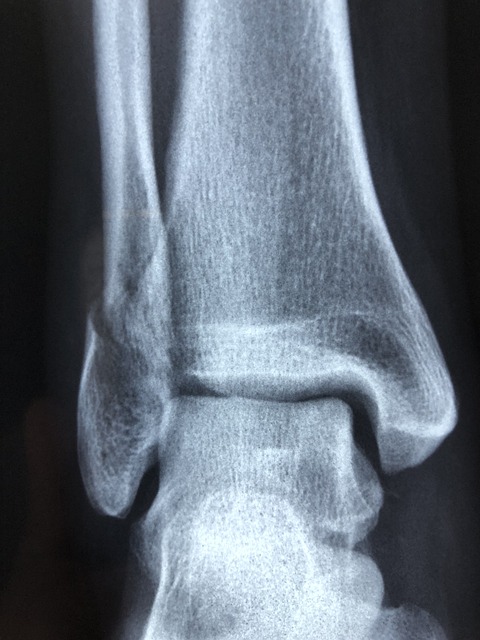

3일 후, 저는 정형외과에 두 번째 진료를 받으러 갔습니다. 의사는 다시 X-레이를 찍어보고자 했습니다.

새롭게 찍은 X-레이에서는 미세한 실금이 있는 것으로 나타났습니다. 의사께서는 정확한 진단을 위해 CT 스캔을 권고하셨습니다.

따라서 종골골절을 정확히 진단하기 위해서는 CT 스캔이 필요할 수 있습니다.

CT 스캔은 뼈와 주변 조직을 더 자세히 살펴볼 수 있어 더 정확한 진단과 치료를 제공할 수 있습니다.